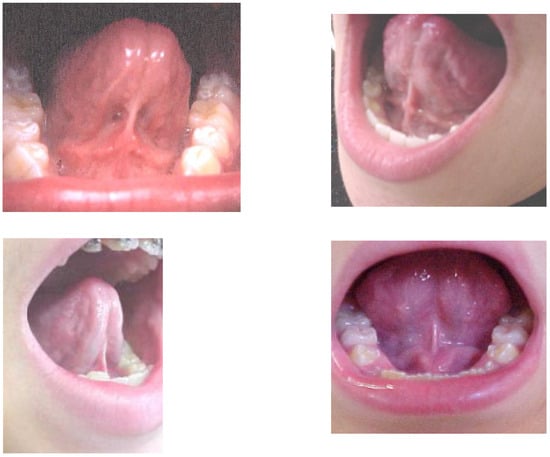

- did not allow adequate movement of the tongue;

- had an insertion in the inferior alveolar ridge or beneath;

- did not allow tongue suction on the palate even if there was an insertion in the midline under the tongue;

- when the tongue was raised the shape of the tip was more square;

- when the tip of the tongue was raised toward the palate only the edges can raise;

- for the tongue to reach the palate the patient needed to almost close the mouth;

- when the tongue is sucked up on the palate the distance between the incisal edges was less than 13mm (Figure 2).